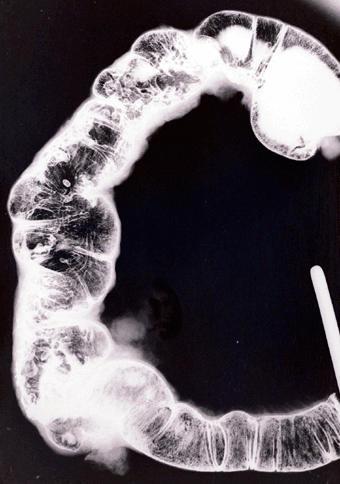

克罗恩(Crohn)病(肠)

伴有微小胃病变的小肠、大肠克罗恩病的切除病例

Tokyo Pref., 国立癌中心中央病院和九州癌中心共同完成

炎症性・溃疡性疾患/克罗恩病

大肠/占据大肠的2个以上区域

X线